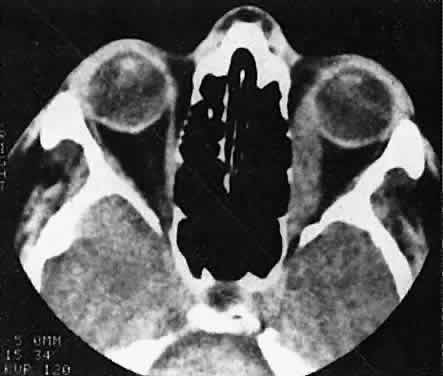

Orbital myositis may represent a greater proportion of cases of IIPT in childhood than in adulthood, and involvement of multiple extraocular muscles may occur more frequently in children than inadults. In orbital myositis, early diplopia and increased discomfort with attempted eye movement are typical symptoms. CT may show enlargement of one or more extraocular muscles in one or both orbits (Figs. 21 and 22). When a single muscle is involved, the specter of a primary or metastatic neoplasm within the muscle may be raised. However, external inflammatory signs, considerable pain and limited motility, and an explosive onset of symptoms within 24 hours all suggest orbital myositis. The uniform enlargement of the muscle, including its tendinous insertion (see Fig. 22), also helps distinguish the process from a neoplasm, which might be expected to produce a more focal, globular expansion. Echography may support the diagnosis of inflammation by showing edema in the episcleral space as a relative sonolucency between the scleral and orbital fat echoes (Fig. 23). Its CT counterpart is an increase in the radiodensity and thickness of the ocular tunica.

Fig. 21. A. This 16-year-old boy had acute onset of bilateral proptosis, pain, diplopia, chemosis, and conjunctival injection. B. Bilateral enlargement of the superior and medial rectus and inferior oblique muscles. Other sections showed similar involvement of other extraocular muscles.